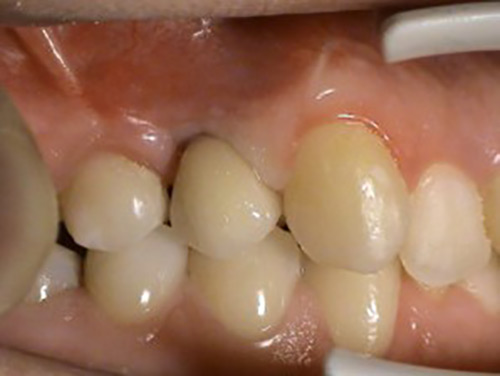

1. PHASE – implant insertion

2. PHASE – state before making immediate impressions